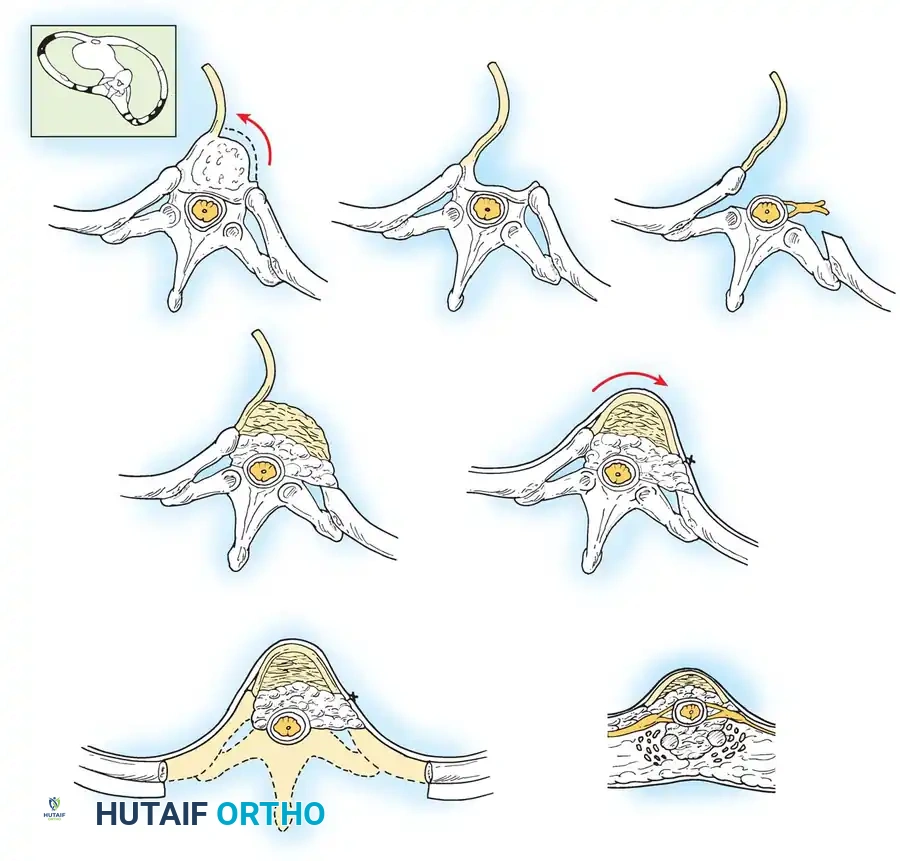

To mobilize a rigid adult spine, posterior osteotomies are frequently required. The choice of osteotomy depends on the degree of correction needed:

- Smith-Petersen Osteotomy (SPO) / Ponte Osteotomy: Involves resection of the facet joints and ligamentum flavum. Provides approximately 5-10 degrees of sagittal correction per level and significant coronal flexibility.

- Pedicle Subtraction Osteotomy (PSO): A three-column closing wedge osteotomy through the pedicles and vertebral body. Indicated for sharp, angular kyphotic deformities or severe fixed sagittal imbalance. Provides 25-35 degrees of lordosis at a single level.

- Vertebral Column Resection (VCR): Complete resection of one or more vertebral segments. Reserved for the most severe, rigid, and complex multiplanar deformities.

Fig. 41-14 Schematic representation of a posterior column osteotomy and concurrent thoracoplasty. Resection of the prominent rib segments on the convexity not only improves cosmetic appearance but provides excellent autograft for the fusion bed.